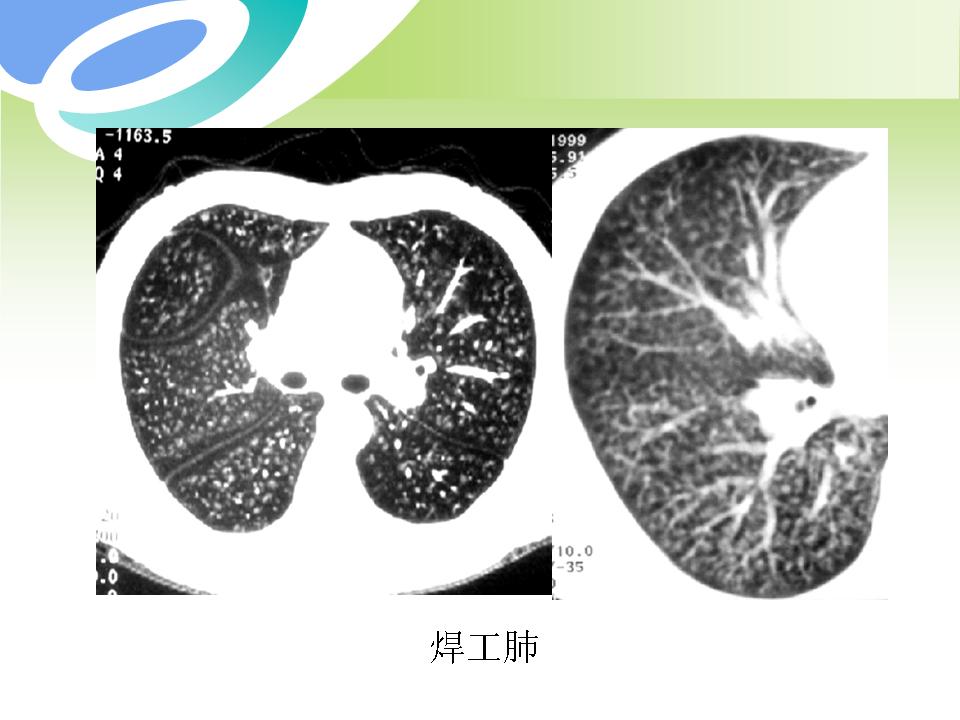

肺部病变的CT基本征象